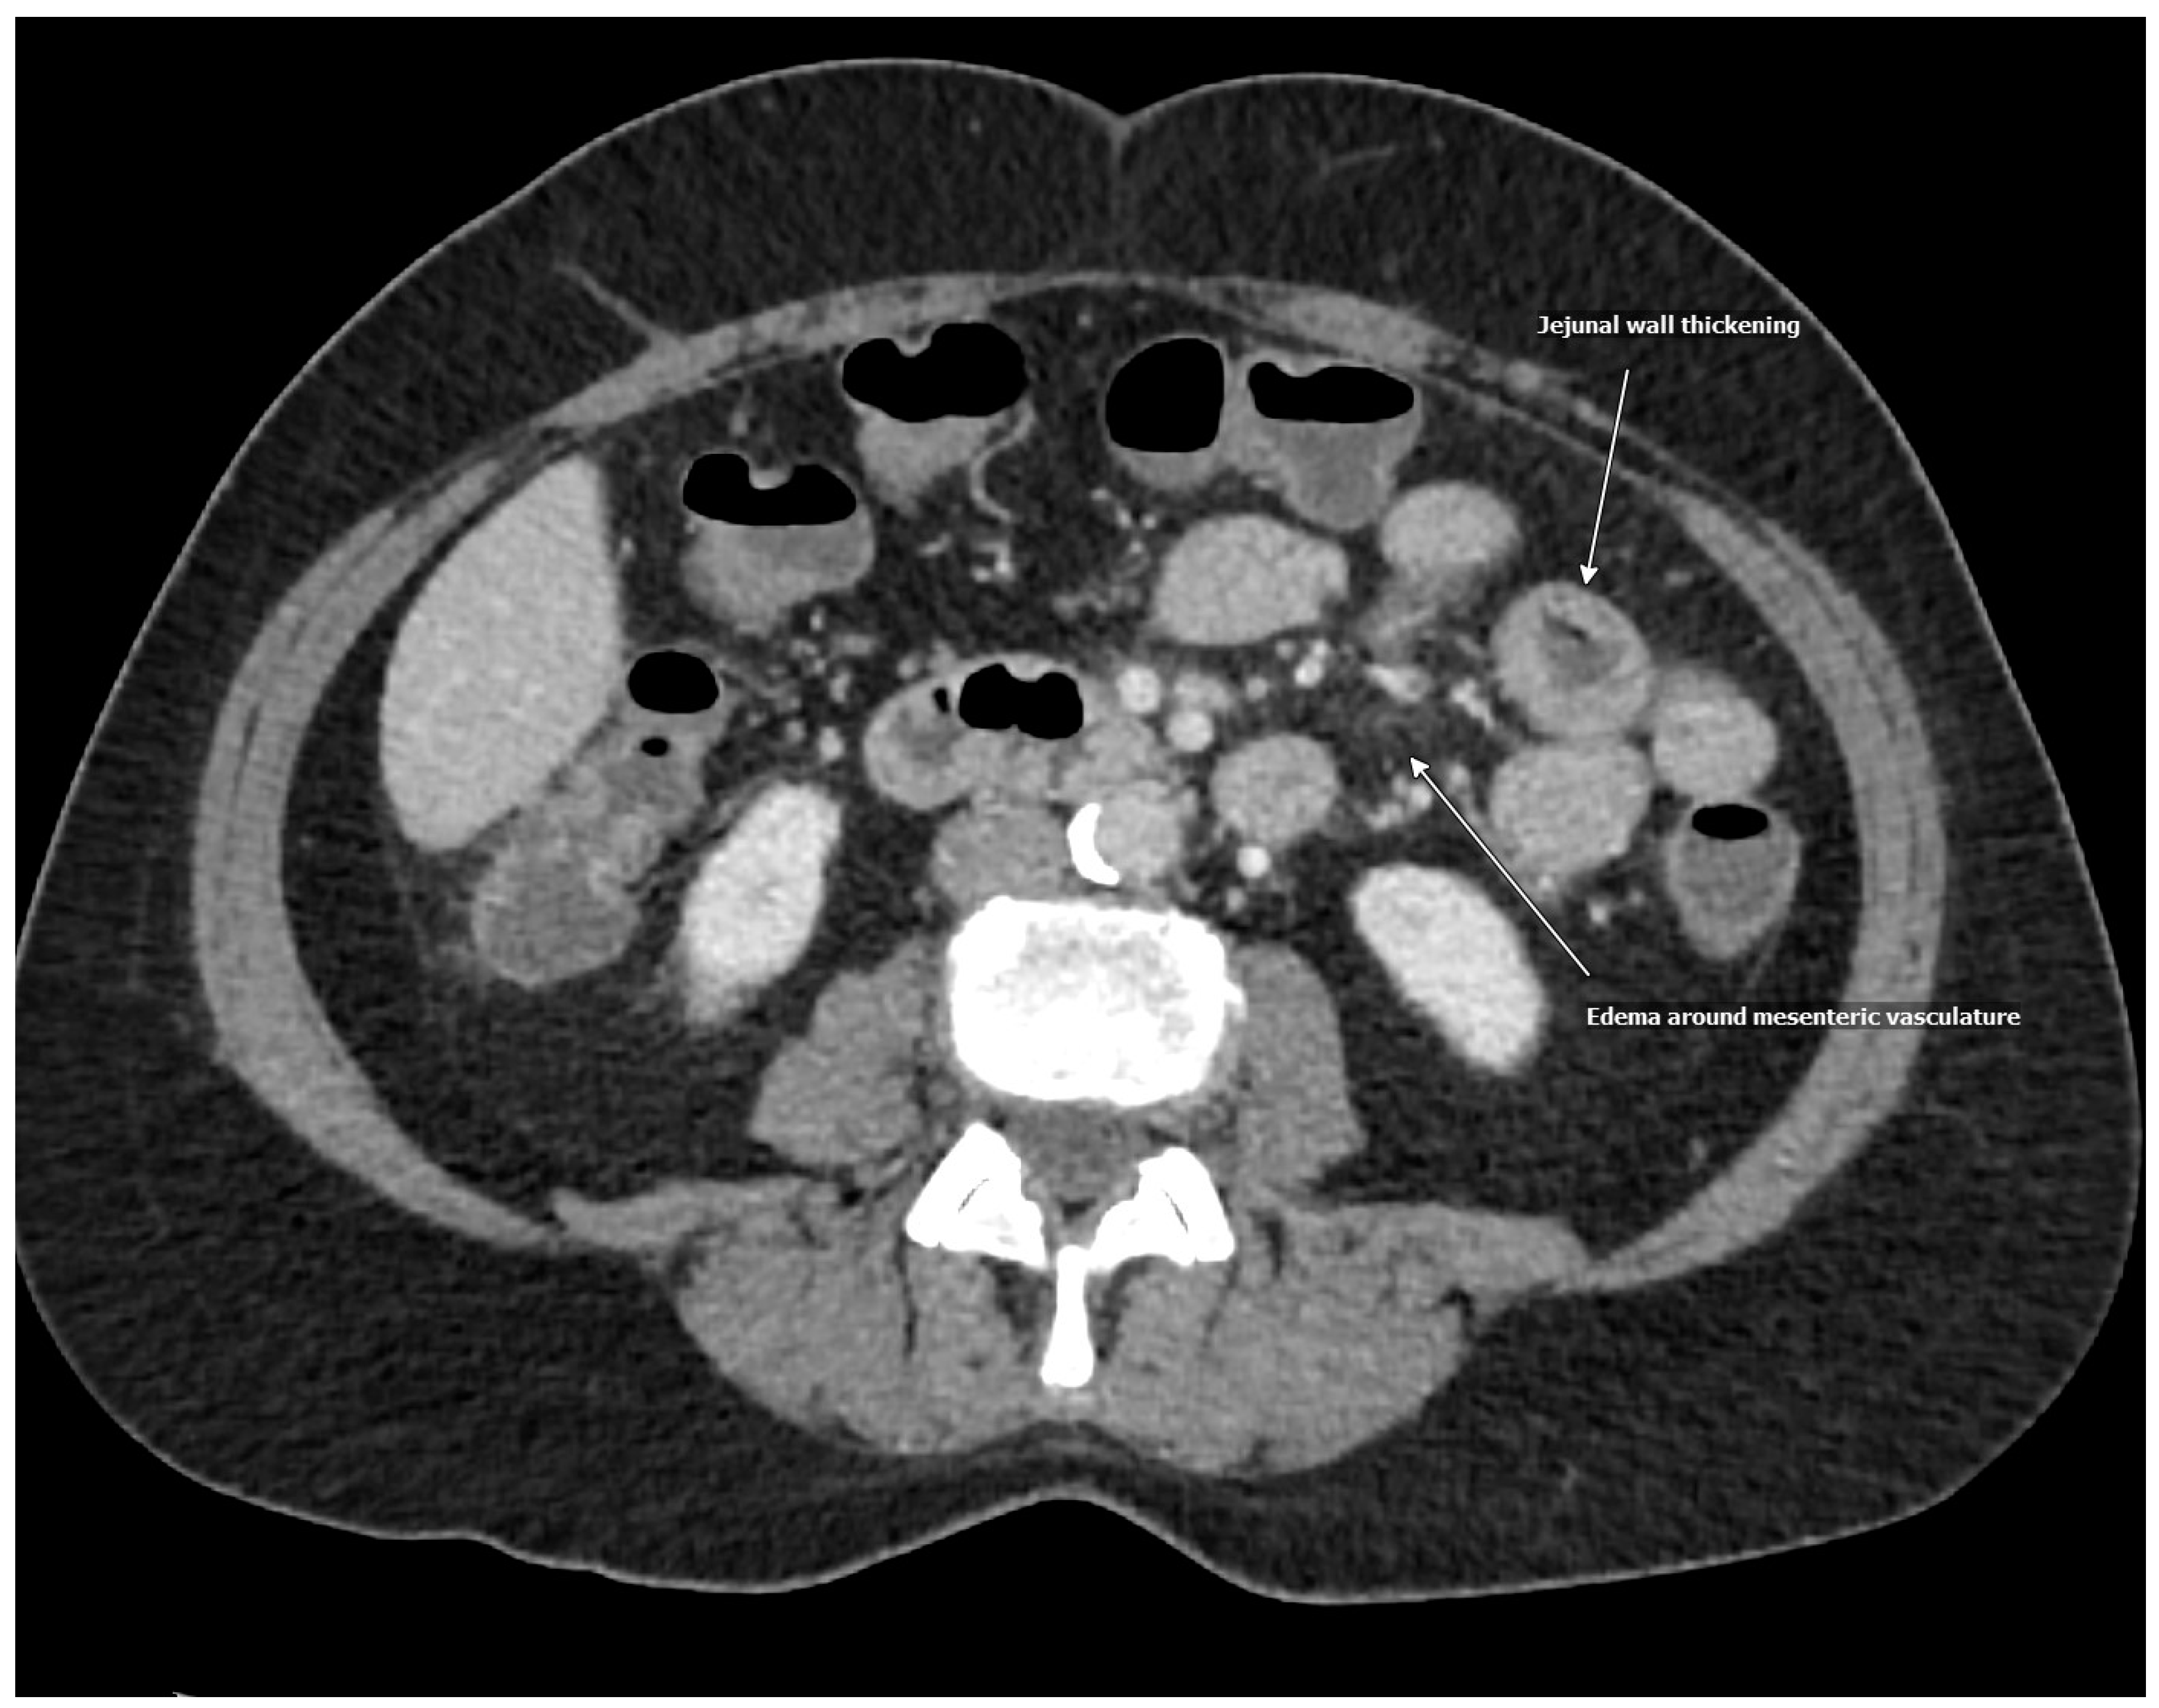

| CTAP | Pancolitis, ileitis, and peri-appendiceal stranding with prominent right lower quadrant mesenteric lymph nodes |

| MRI | Inflammation of the duodenum, jejunum, and colon |